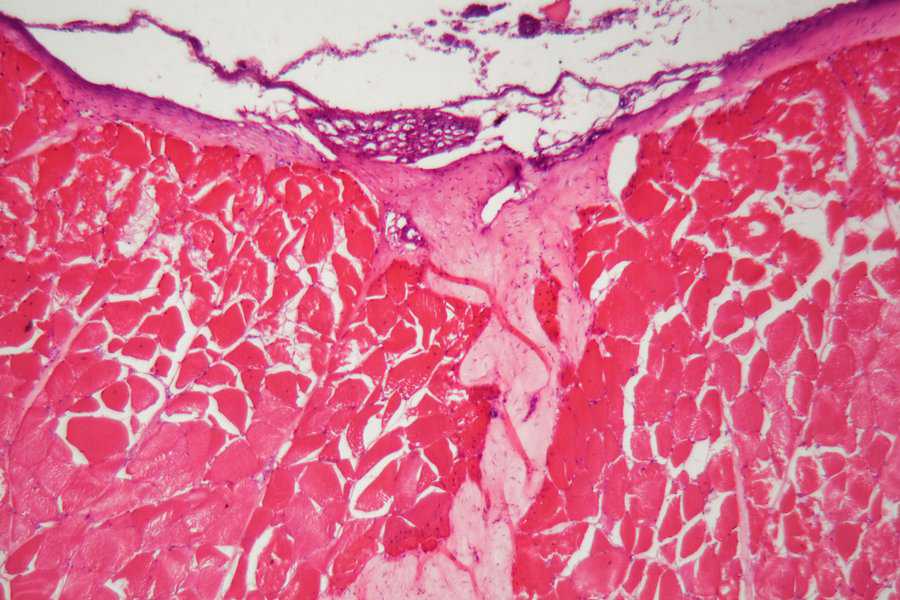

11. Kidney

This image is a light micrograph of a contracted kidney displayed under a microscope. It doesn’t really resemble anything, certainly not a kidney.